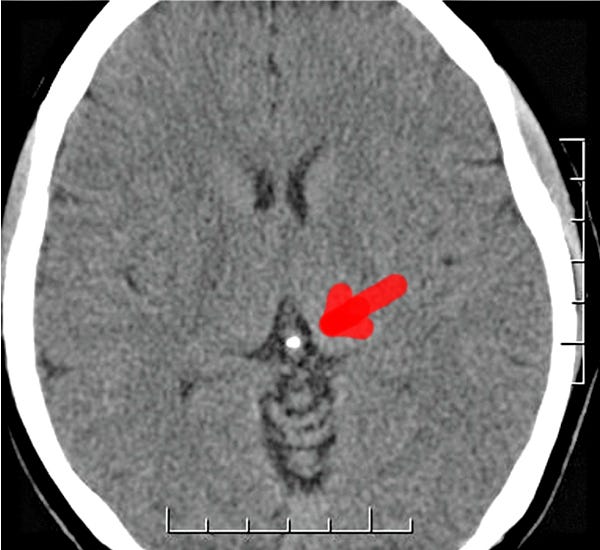

Here's what should alarm everyone: According to a 2023 systematic review and meta-analysis, pineal calcification now affects 33% of teenagers, 60% of 40-year-olds, and over 70% of seniors.[1] Even more disturbing—8% of children under 10 already show calcification on brain scans. In some populations, the rates are even higher, with certain regions showing up to 85% calcification in adults.

The mechanism is insidious: The pineal naturally contains hydroxyapatite crystals—the same calcium-phosphate compound in teeth and bones. These crystals give the healthy pineal its "sand-like" appearance on scans and may serve a biological function (some theorize they're piezoelectric, converting mechanical pressure to electrical signals). But fluoride has an exceptionally high affinity for hydroxyapatite. Every time you drink fluoridated water (0.7-1.2 ppm in most US cities), brush with fluoride toothpaste (1,000-1,500 ppm), or eat processed foods made with fluoridated water, you're feeding a 24/7 calcification process.

Month 12: Possible measurable reduction in calcification on CT scan